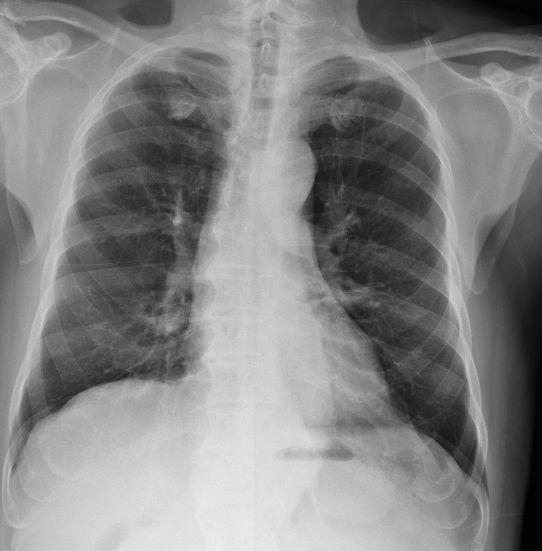

腺癌在早期一般没有明显的临床症状,往往在胸部X线检查时发现。癌肿生长较缓慢,但有的病例较早即发生血道转移,较常在呈现脑转移症状后才发现肺部原发癌肿。肺腺癌的病因与吸烟之相关性不若鳞状细胞癌或小细胞肺癌大,症状从没有症状之X光阴影,到咳嗽,气促,咳血都有可能,若有转移性病灶,则可能并有转移病灶之症状。